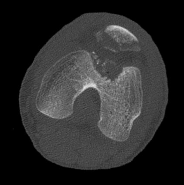

Question 5:

A 32-year-old female presents with progressive knee pain. Imaging reveals an eccentric, lytic, epiphyseal lesion in the proximal tibia extending to the subchondral bone without a sclerotic margin. Biopsy confirms multinucleated giant cells intermixed with mononuclear stromal cells. If targeted medical therapy is initiated prior to surgical curettage, what is the primary mechanism of action of the preferred agent?

The clinical and radiographic presentation is classic for a Giant Cell Tumor (GCT) of bone. Denosumab is a monoclonal antibody frequently used as neoadjuvant or primary medical therapy for aggressive or unresectable GCTs. It binds specifically to RANKL, preventing it from interacting with RANK receptors on osteoclast precursors and the giant cells themselves, thereby profoundly inhibiting osteoclastogenesis and tumor-associated bone destruction.